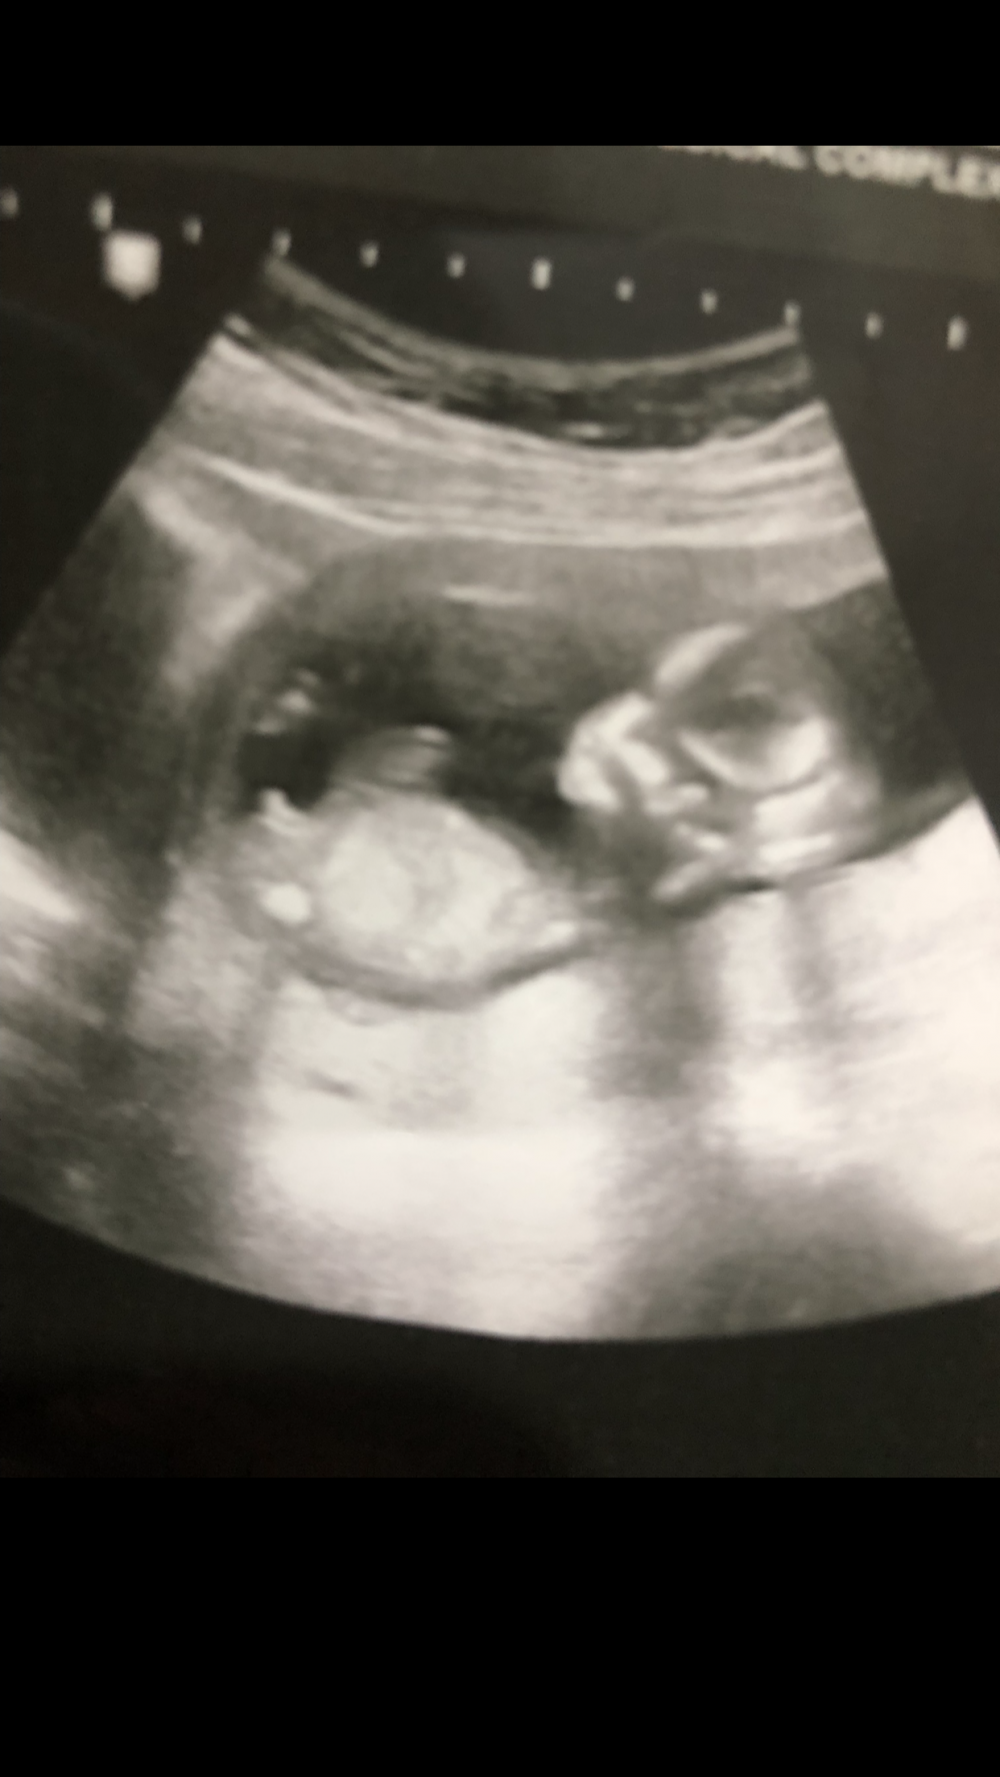

اخطاء السونار كثيره لان بعض الاجهزة قديمه ومو واضحه

احاول انزل السونار